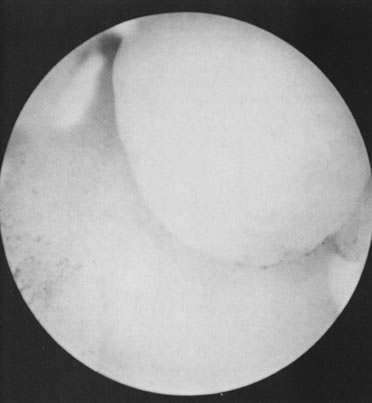

Conventional metroplasty requires major surgery and may jeopardize fertility because of subsequent pelvic adhesions. A longer postoperative interval is required before pregnancy can be established; moreover, cesarean section is needed. For these reasons, hysteroscopic division of the uterine septum is more appealing to patients and physicians; the low morbidity, simplicity, and encouraging pregnancy outcome with this operation make it the treatment of choice for a symptomatic septate uterus (Figs. 32, 33, and 34).35

Fig. 32. Hysteroscopic view of an incomplete uterine septum.

Fig. 33. Hysteroscopic division of the septum.

Fig. 34. Hysteroscopic view of a unified uterine cavity immediately after hysteroscopic division of the septum.